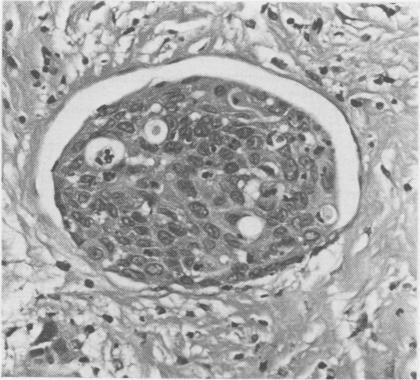

The pathological, cytological, and clinical features of vulvar intraepithelial neoplasia (VIN) are described. The rate of progression of VIN III to an invasive carcinoma is very low and spontaneous regression can occur. These features prevent the drawing of a direct analogy between vulvar and cervical intraepithelial neoplasia. The concept of microinvasive carcinoma of the vulva is discussed, and it is concluded that no satisfactory definition of this entity has been achieved.

本文描述了外阴上皮内瘤变(VIN)的病理、细胞学及临床特征。VIN III进展为浸润性癌的发生率很低,且可发生自发消退。这些特征使得外阴上皮内瘤变与宫颈上皮内瘤变无法直接进行类比。文中对外阴微浸润癌的概念进行了讨论,得出的结论是尚未对该实体达成令人满意的定义。